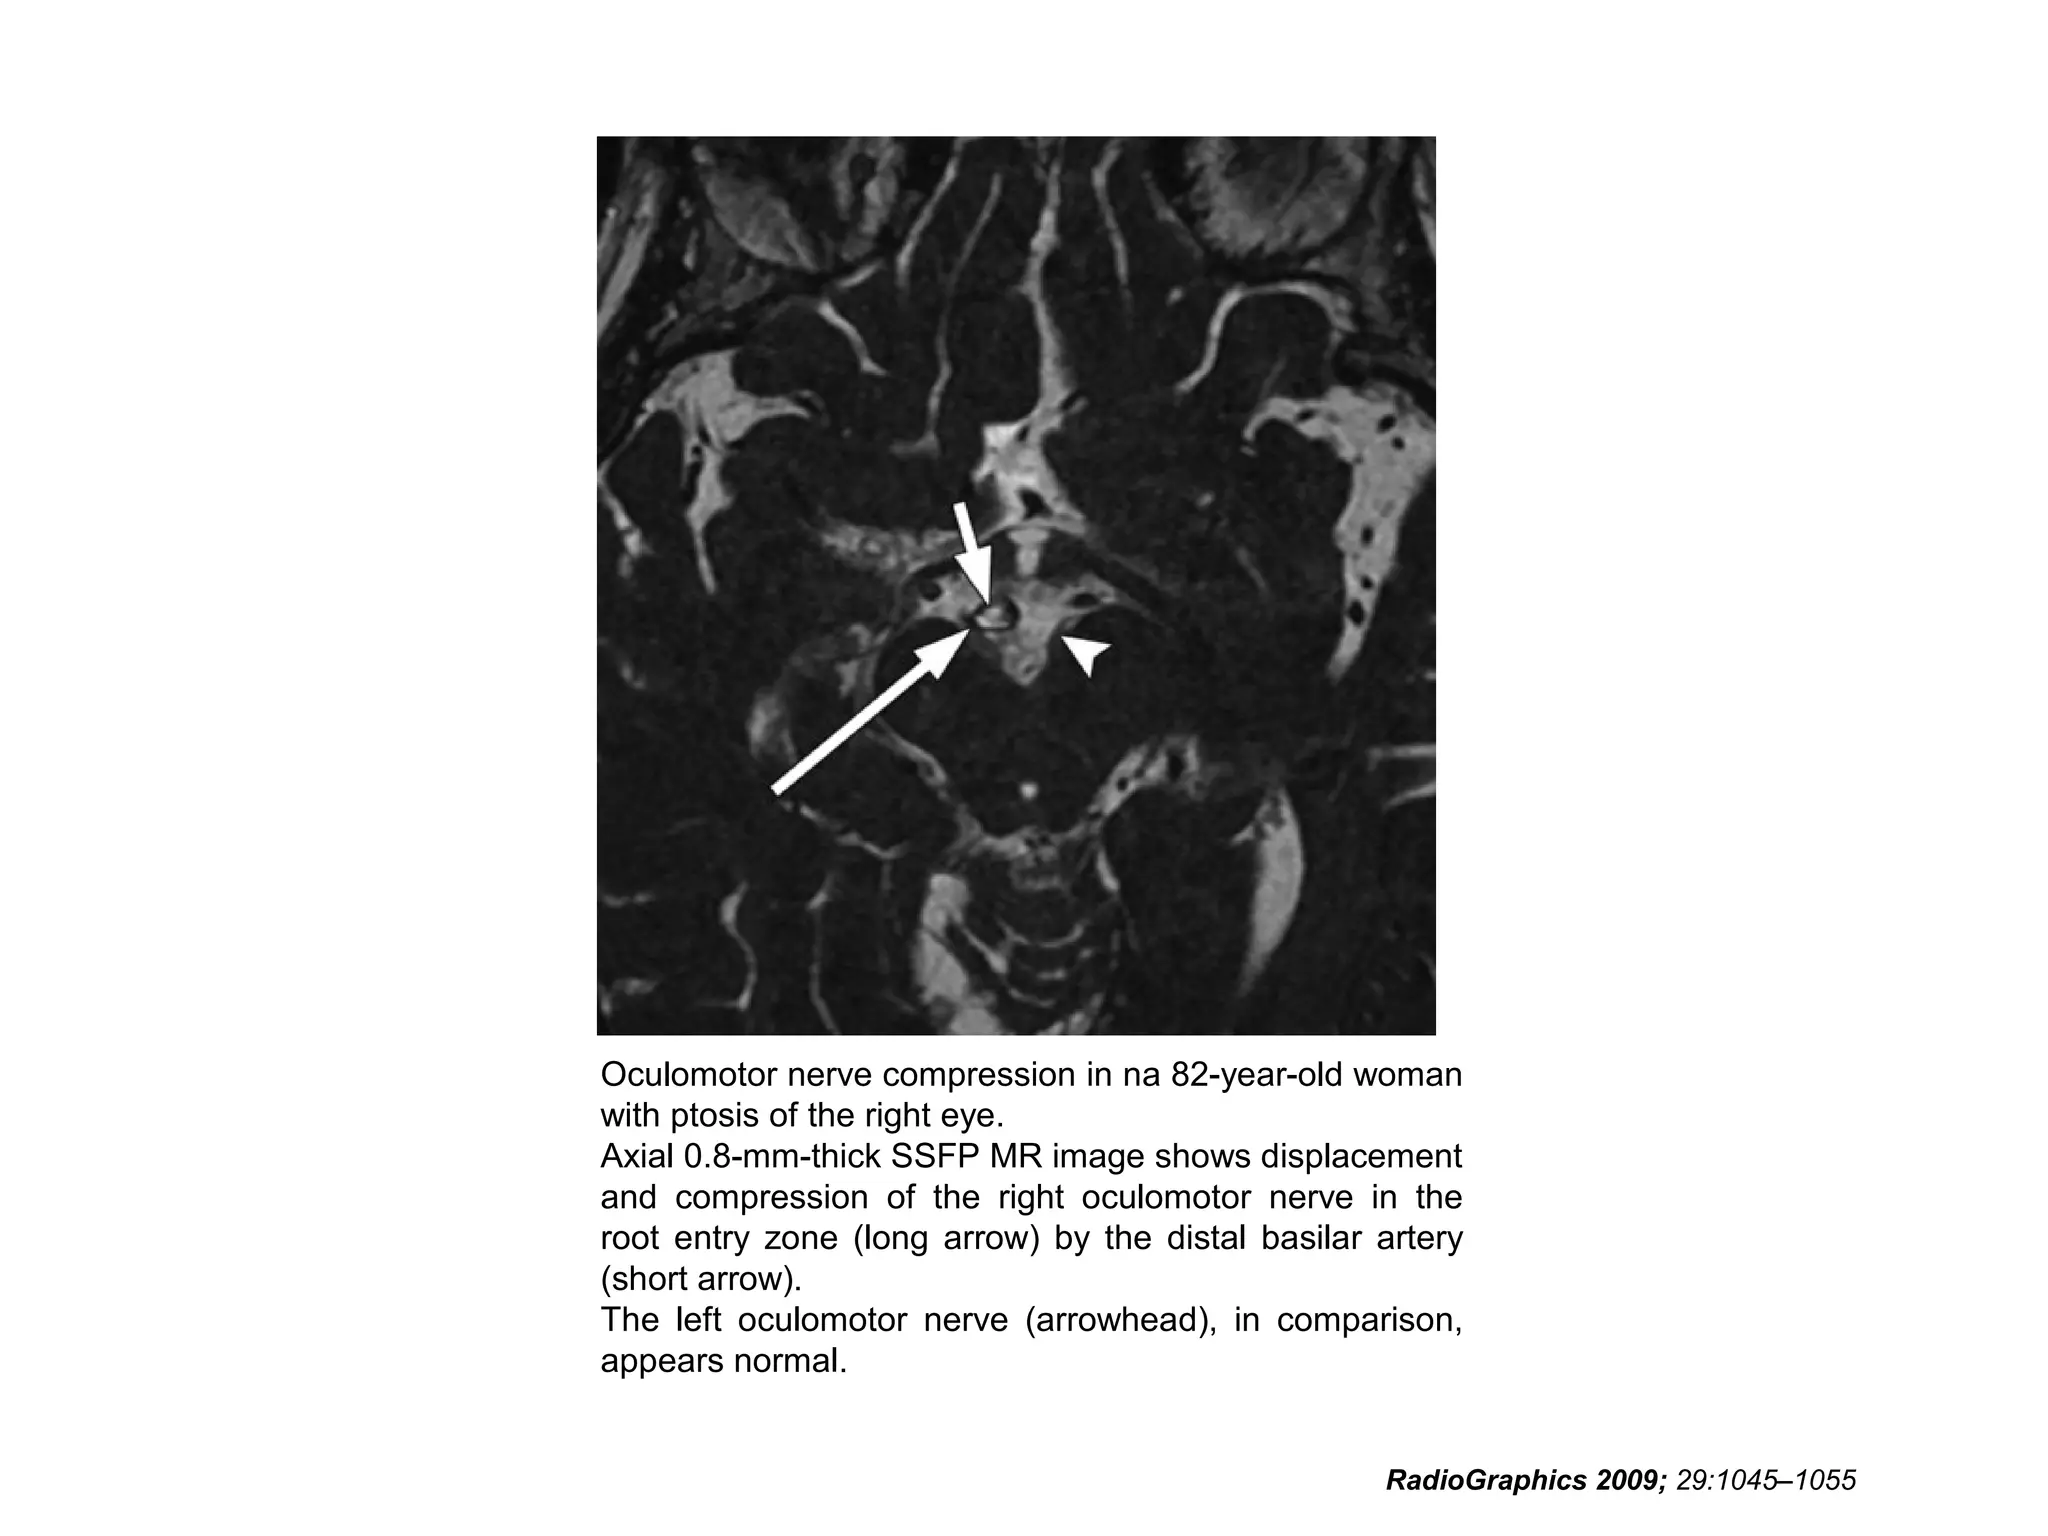

Oculomotor nerve compression in na 82-year-old woman

with ptosis of the right eye.

Axial 0.8-mm-thick SSFP MR image shows displacement

and compression of the right oculomotor nerve in the

root entry zone (long arrow) by the distal basilar artery

(short arrow).

The left oculomotor nerve (arrowhead), in comparison,

appears normal.

RadioGraphics 2009; 29:1045–1055